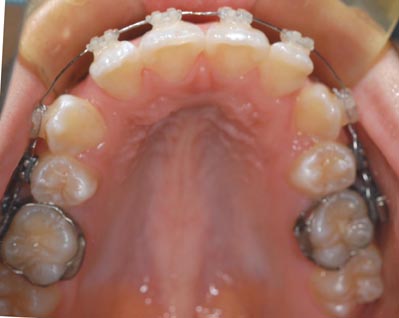

1.叢生(乱ぐい歯) 歯が重なり合ってでこぼこしています

治療前

上顎両側4番を抜歯

下顎両側4番も抜歯